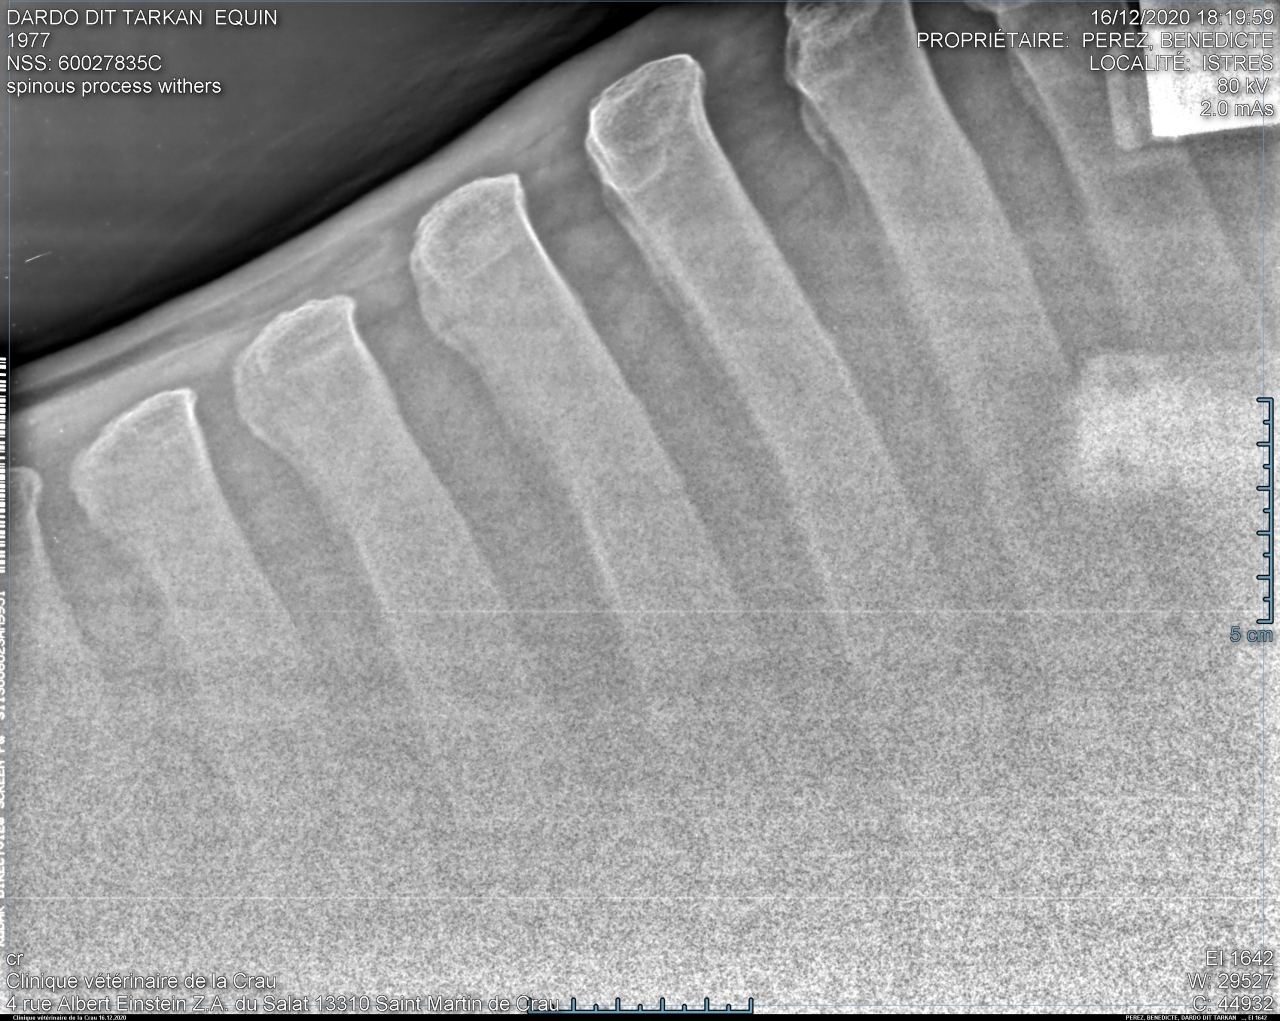

| Dire merci1 | allez pcq je suis sympa en spoiler pour pas polluer et pcq il y a mon nom de famille aussi ![]() |

| Dire merci | Ah ouais punaise lui c’est costaud! ![]() La mienne y a des rétrécissements des espaces mais rien ne se touche. |

| Dire merci | Ah oui !! ![]() Du coup..... Dardo dit Tarkan ??? |

Par takhan : le 11/04/24 à 18:29:23

| Dire merci | Dardo oui mais la véto a écrit tarkhan alors que c'est bien takhan ![]() Puis a mon avis depuis ça s'est aggravé. Si je farfouille je devrais pouvoir retrouver celles de 2016 pour voir l'évolution en quelques années. ![]() |